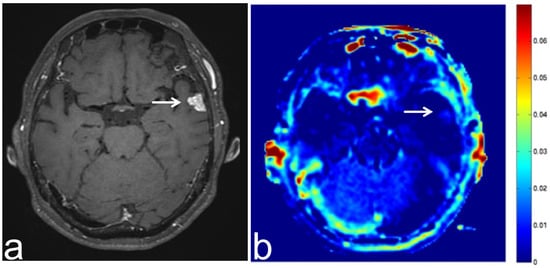

8.1. Radiation Necrosis

7.1. Sphenoid Sinus Mucocele

7.2. Solitary Fibrous Tumor